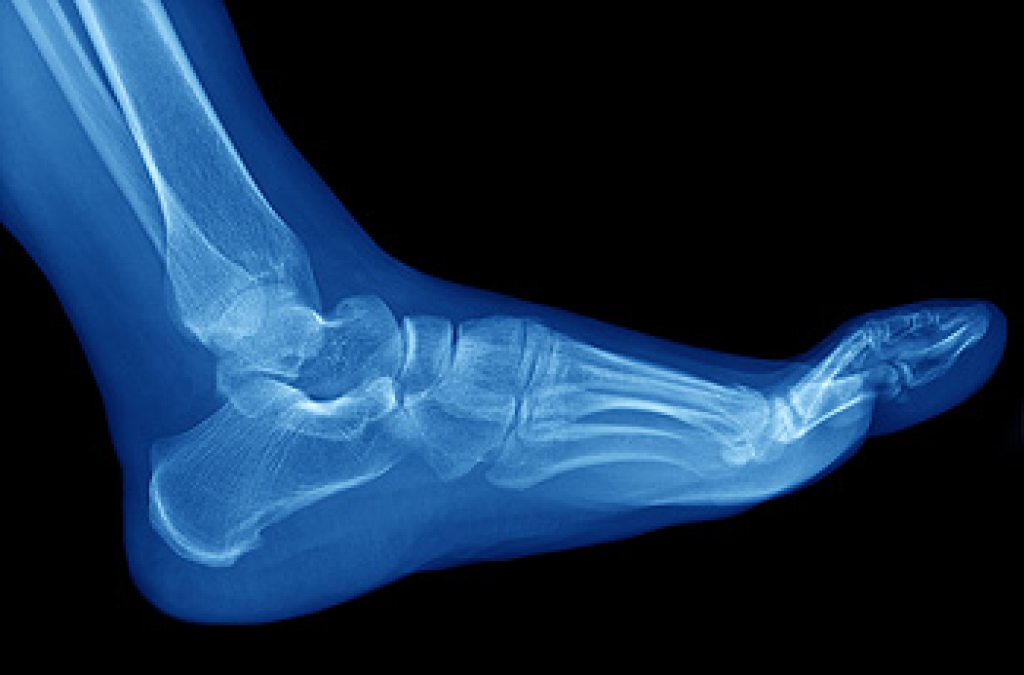

The Achilles tendon is a tendon that connects the lower leg muscles and calf to the heel of the foot. It is the strongest tendon in the human body and is essential for making movement possible. Because this tendon is such an integral part of the body, any injuries to it can create immense difficulties and should immediately be presented to a doctor.